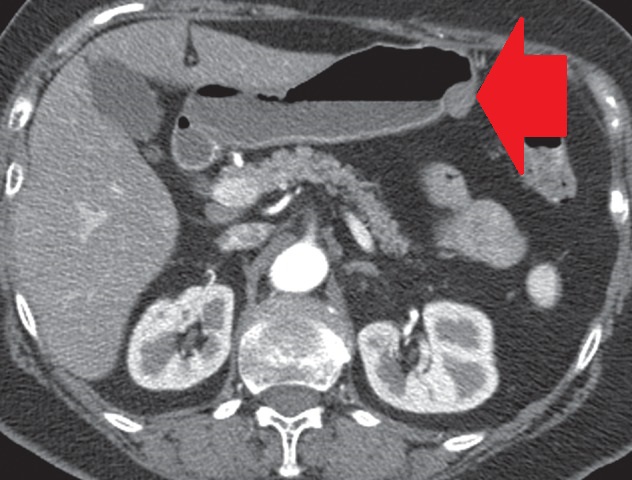

Abdominal CT scan. Red outline – Inflammatory fibroid polyp of the duodenum (Courtesy Dr. V. Penopoulos)